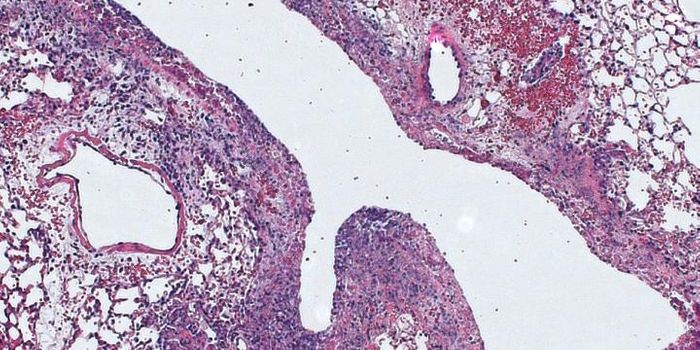

MAY 21, 2018CancerThe malarial parasite expresses a protein, VAR2CSA, that binds to chondroitin sulfate (CS) found on both placental and c ...